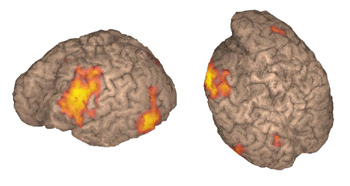

Niña diestra de 11 años de edad con epilepsia intratable sometida a resección frontal izquierda dos años atrás para control de las convulsiones. La persistencia de las convulsiones dio lugar a este examen de IRMf para una nueva evaluación. Las imágenes demostraron una activación obtenida a partir de una "tarea de generación de verbos". El estudio mostró el área de Broca y parte del área de Wernicke (área 37 de Brodmann), las cuales se cree que funcionan como depósito de palabras. Se realizó una segunda resección en función de estos hallazgos. La paciente no experimentó afasia postoperatoria y hasta la fecha no ha vuelto a tener convulsiones.

Estas imágenes complementan el caso 2 presentado en "Representación de superficie". La activación se obtiene con una tarea de "generación de verbos" en el área de Wernicke, no solo a lo largo de la superficie cortical sino de forma profunda a lo largo de las circunvoluciones.